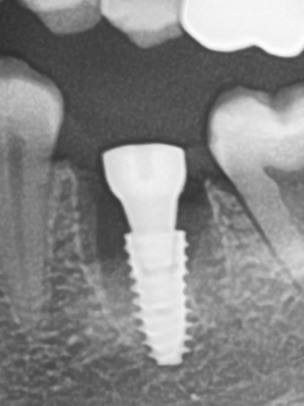

Одномоментная имплантация — Исламов Л.А.(10.11.2025)

Одномоментная имплантация системой Osstem(Ю. Корея), подшит трансплантат с бугра(для увеличения объема мягких тканей), установлен формирователь десны. Через 3 месяца установлена коронка из диоксида циркония на винтовой фиксации